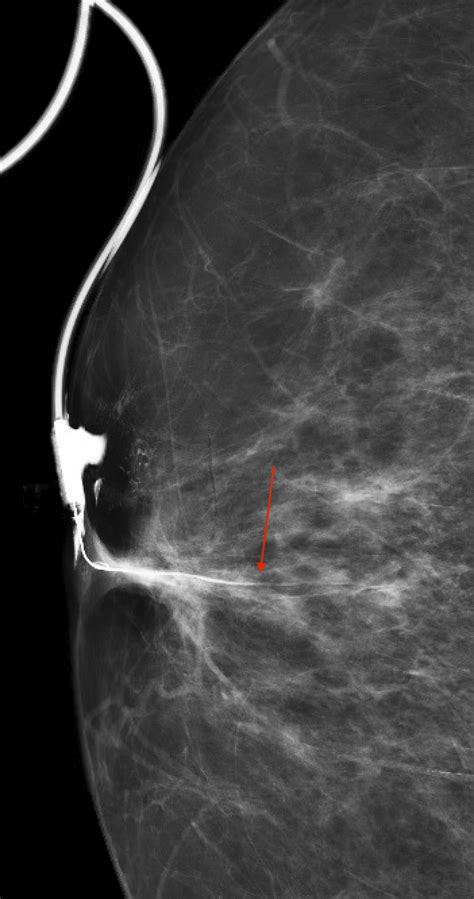

• Mammogram: An X-ray of the breast to detect any masses or abnormalities.